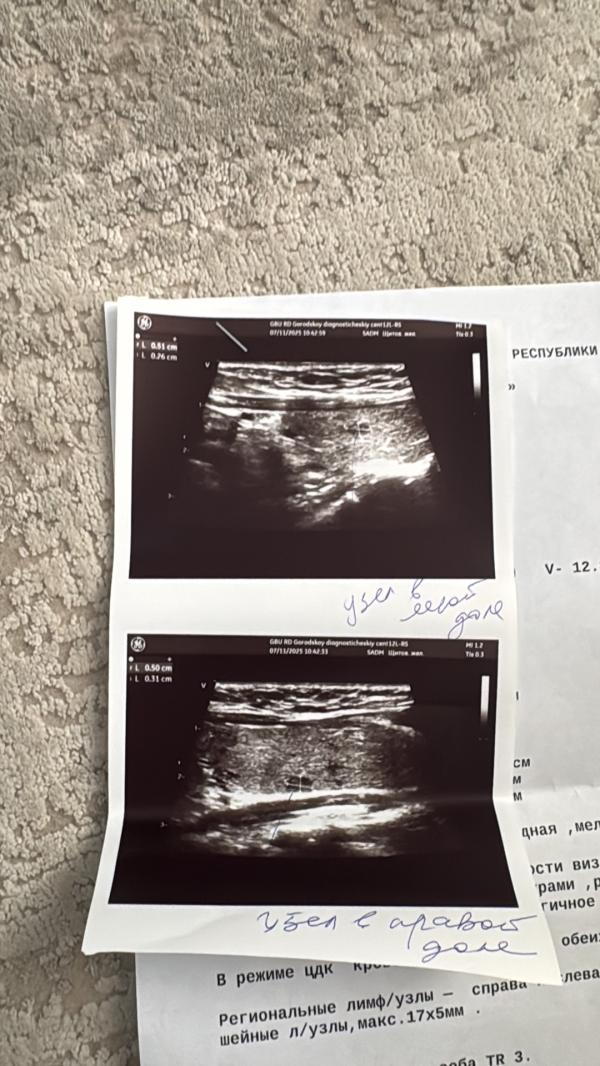

post image 1

post image 2

TR3 редко онко. Но всё-таки лучше к врачу и на пункцию при необходимости